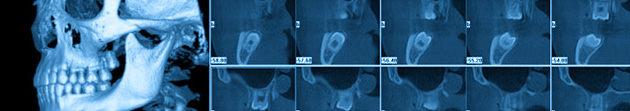

Three Dimensional Cone Beam CT Scans (CBCT)

A traditional x-ray is only 2 dimensional but a computerized assisted image will give 3 dimensional information and even more date to diagnose and plan your case. You will get the scan at specialized facility and then your specialist will receive and review the data. This will better plan your surgical case and if there any needed changes we update you and educate you of any changes in your case plan.